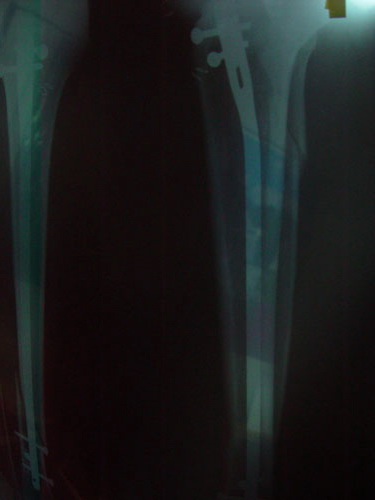

เมื่อวาน 13 มีค.54 ได้มีโอกาศไปร่วมแข่งไซเคิล ที่เมืองสอง โอ้โห..จัดใหญ่เหมียนเดิม แต่อยู่ไม่ถึงจบการแข่งขัน ต้องไปดูแลป๋าเสี้ยว แม่เมาะ ซึ่งประสบอุบัติเหตุ ขาหัก3ท่อน เกือบไปซะแล้ว...

...มาดูความรุนแรงของป๋าเสี้ยวเสียหน่อย...รักษาสุขภาพนะครับ...